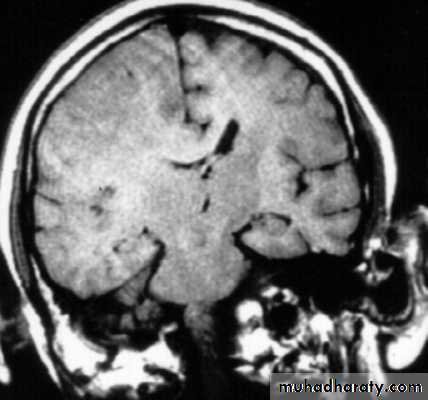

c. Intracerebral Haematoma

This is the least common of traumatic haematoma.They are due to areas of traumatic contusion coalescing into a contusional haematoma.

Disrupted cerebral tissue release thromboplastins that potentiate haemorrhage.

CT scan: appear as hyperdence lesions with associated mass effect and midline shift.Large intracerebral haematomas should be evacuated unless the patient’s neurological state is improving.

Small inracerebral haematomas may not require removal, but be aware that they can expand.